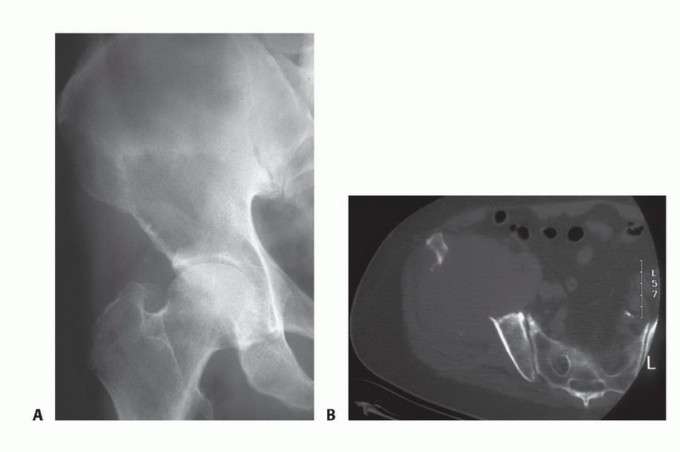

الشكل 2: أ. صورة أشعة سينية تظهر كسرًا مرضيًا في الورك لدى أنثى تبلغ من العمر 69 عامًا ولديها تاريخ معروف بسرطان الثدي. ب. أجريت عملية استبدال نصفي للورك خلال 24 ساعة من حدوث الكسر، ولكن صور الأشعة السينية بعد الجراحة أظهرت نقيلة إضافية أسفل طرف جذع الطرف الاصطناعي (ج) لم يتم اكتشافها بسبب سوء جودة صور الأشعة السينية قبل الجراحة ولأن صور الأشعة السينية للعظم بالكامل لم تُجرَ قبل الجراحة. د. بينما كانت لا تزال في المستشفى، عانت من كسر مرضي في تلك الآفة أثناء نقلها من سريرها إلى كرسي استلقاء.